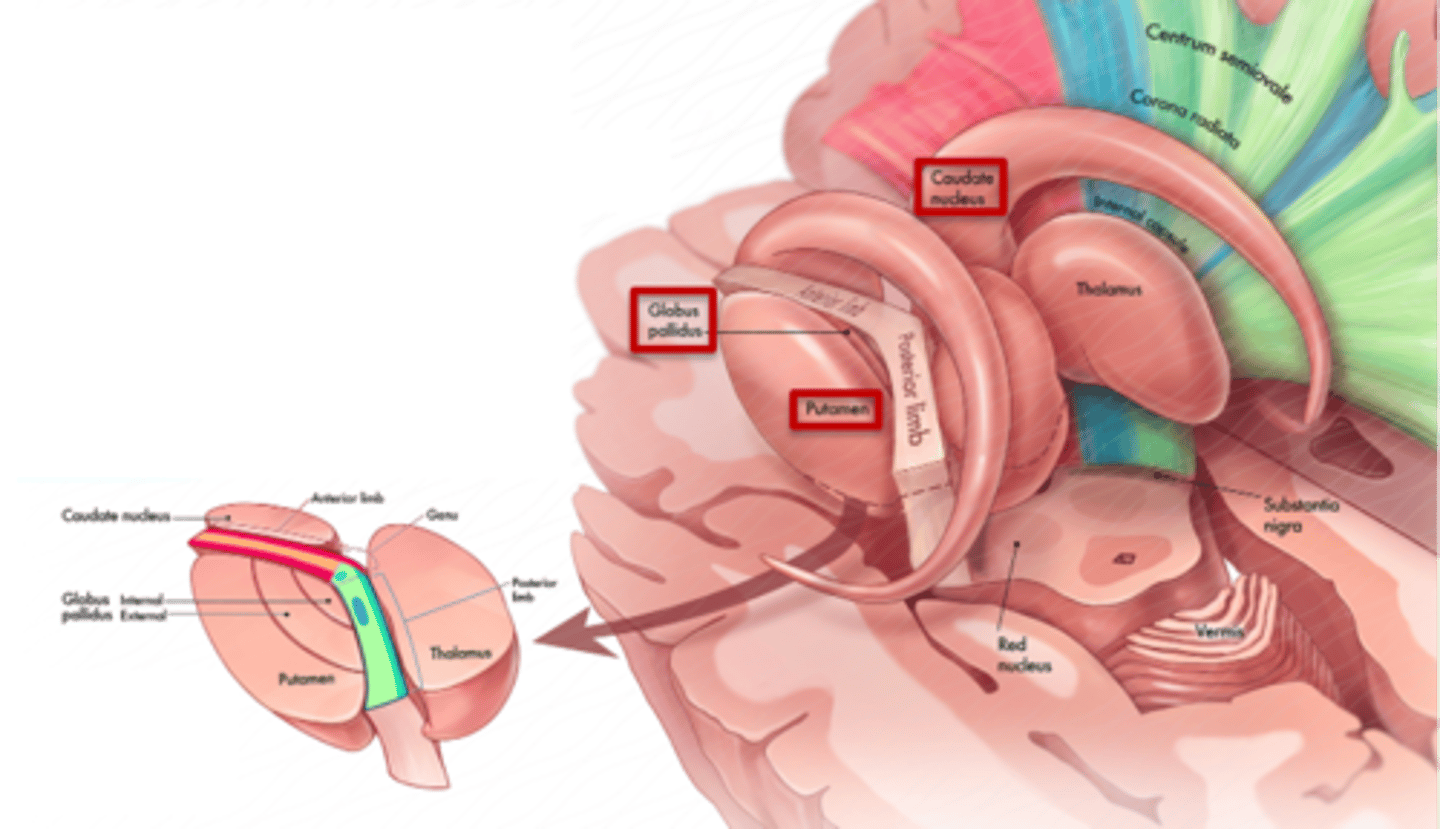

what are 3 key white matter structures found in the cerebrum?

1. corpus callosum

2. corona radiata

3. internal capsule

what cerebral white matter structure is a large bundle of nerve fibers that connects the left and right cerebral hemispheres, allowing them to communicate?

corpus callosum

what is the fan-shaped cerebral white matter sheet that is continuous ventrally with the internal capsule?

corona radiata

what cerebral white matter structure is a tract that carries sensory and motor information to and from the cerebral cortex?

internal capsule

what cerebral white matter structure is found between the basal ganglia?

internal capsule

what are the 3 regions of the internal capsule?

1. anterior limb

2. genu

3. posterior limb

what cerebral gray matter structure is a collection of subcortical nuclei primarily involved in motor control?

basal ganglia

what cerebral gray matter structure has a gate-keeping mechanism for the initiation of motor movement (choosing which actions to allow and which to inhibit)?

basal ganglia

what cerebral gray matter structure has roles in motor learning, executive functions, behaviors, and emotions?

basal ganglia

what are the 3 parts of the basal ganglia? what runs between them?

1. caudate nucleus

2. putamen

3. globus pallidus

internal capsule

what part of the basal ganglia is the C-shaped structure that is most medial?

caudate nucleus

what part of the basal ganglia is medial to the putamen?

globus pallidus

the putamen and globus pallidus of the basal ganglia are collectively called the _______________ nucleus

lentiform